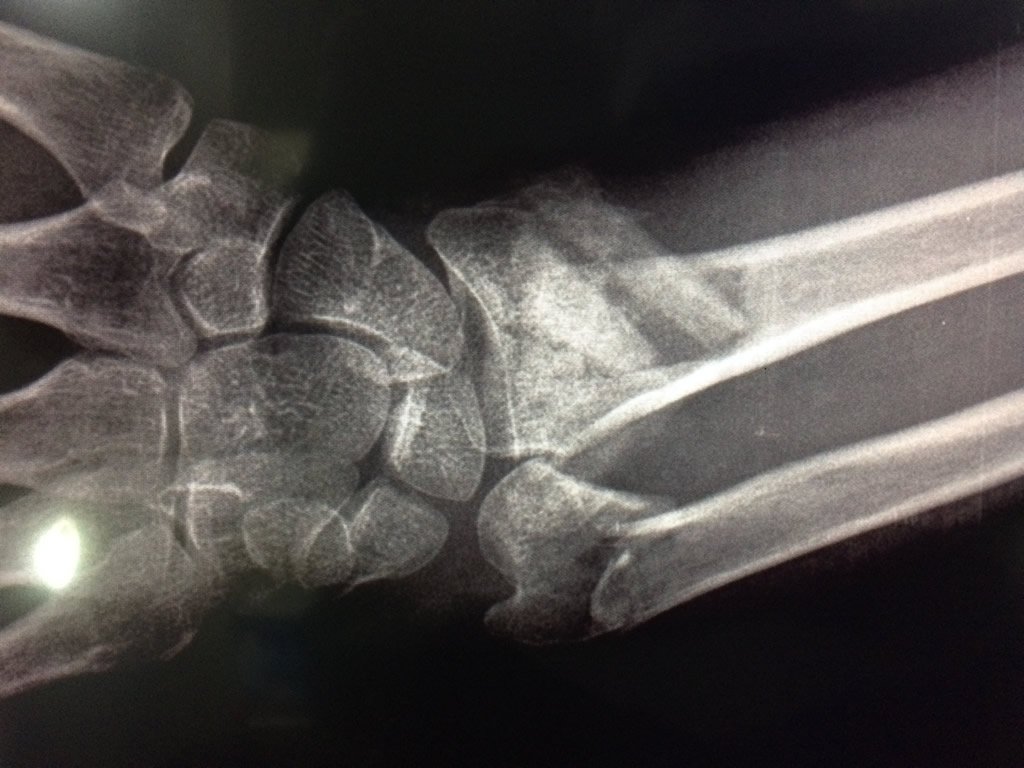

Cirugías de Codos - Cirugías de Muñecas y Manos

Los procedimientos más comunes en cirugía de la mano son aquellos destinados a reparar traumatismos, incluyendo lesiones de tendones, nervios, vasos sanguíneos, y articulaciones; huesos fracturados; y quemaduras, cortes, y otros daños de la piel.